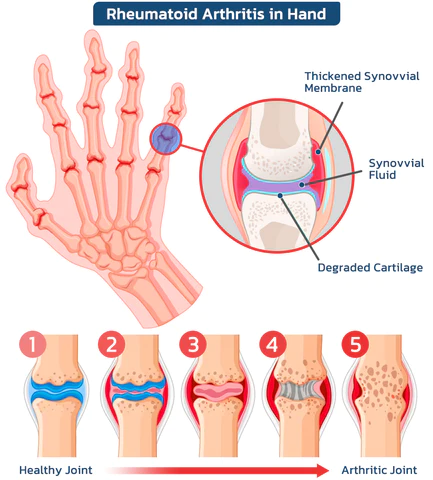

🔍 Factors that contribute to the development of common arthritis

Common factors in the development of arthritis include aging, genetic factors, joint injuries, overuse of joints, obesity, osteoporosis, certain diseases and conditions, and gender. These factors may increase the risk of arthritis.

The dangers of arthritis?

According to estimates by the World Health Organization (WHO), approximately 300 million people worldwide suffer from arthritis. Less severe cases include arthritis, rheumatism and gout, with symptoms including pain, stiffness, swelling, difficulty with movement, fatigue and loss of range of motion. Severe cases can lead to joint deformities, fever and severe joint pain, resulting in long-term pain and disability. In extreme cases, orthopedic conditions can even lead to life-threatening complications.

Common Orthopedic Joint Symptoms

Arthritis refers to inflammatory diseases that occur in the joints and surrounding tissues of the human body and are caused by inflammation, infection, degeneration, trauma, or other factors. They can be divided into dozens of types. Clinical manifestations include redness, swelling, heat, pain, dysfunction, and deformity of joints, which can lead to joint disability and affect the quality of life of patients.